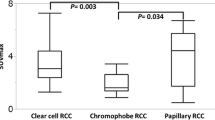

Patient background factors and Fuhrman grades of the 31 cRCCs in 31 patients are summarized in Table 1. No significant difference was found in patient age (P = 0.69) or gender (P = 0.95) between the high- and low-grade tumours. Of the 31 patients, two had a Fuhrman grade 1 tumour, 15 had a grade 2, 13 had a grade 3, and one had a grade 4 tumour. PET/CT images of Fuhrman grade 2 and 3 cRCCs are illustrated in Figs. 1 and 2, respectively. The maximum cRCC diameter ranged from 26 to 152 mm, with a mean size of 67.4 ± 32.3 mm. The maximum diameter of the high-grade tumours (range 35–152 mm, mean 79.7 ± 31.0 mm) was greater than that of the low-grade tumours (range 26–129 mm, mean 57.2 ± 30.4 mm) (P = 0.02) (Fig. 3).

Correlation between SUV and pathological grade

Logistic regression analysis demonstrated that only the tumour-to-liver SUV ratio was a significant parameter for differentiating high-grade from low-grade tumours (P = 0.007 and 0.010 for observers 1 and 2, respectively). The mean tumour SUVmax, tumour-to-liver SUV ratio, and tumour-to-spleen SUV ratio are summarized in Tables 2 and 3. The mean tumour-to-liver and tumour-to-spleen SUV ratios were significantly higher for Fuhrman grade 3 compared to grade 2 tumours (P < 0.05). Intraclass correlation coefficients demonstrated substantial to almost perfect agreement between the measurements by the two observers (Table 2). The mean tumour SUVmax, tumour-to-liver SUV ratio, and tumour-to-spleen SUV ratio for the high-grade tumours were greater than those for the low-grade tumours (P = 0.0004–0.0029) (Figs. 5, 6 and 7). Interobserver reproducibility was excellent for tumour SUVmax, tumour-to-liver SUV ratio, and tumour-to-spleen SUV ratio (intraclass correlation coefficient, 0.78–0.98) (Table 3).